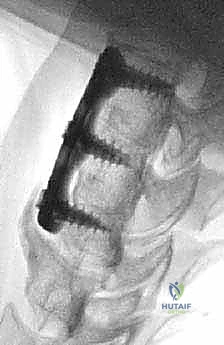

الخطوة 7: التثبيت المعدني (Instrumentation)

لضمان الاستقرار الفوري ومنع حركة الطعم العظمي حتى يكتمل الالتحام (والذي يستغرق أشهراً)، يقوم الدكتور هطيف بتثبيت شريحة معدنية صغيرة من التيتانيوم على الجزء الأمامي من الفقرتين باستخدام براغي دقيقة.